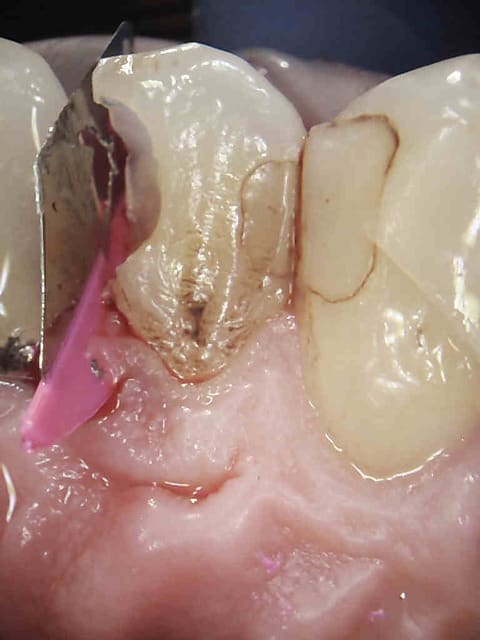

Un peu de Registrans (silicone transparent) et le compo devient facile ;)

ESTELITE QUICK ... ;)

Peux-tu Cingulum décrire le protocole opératoire pour cette belle reconstruction de la face occlusale stp.